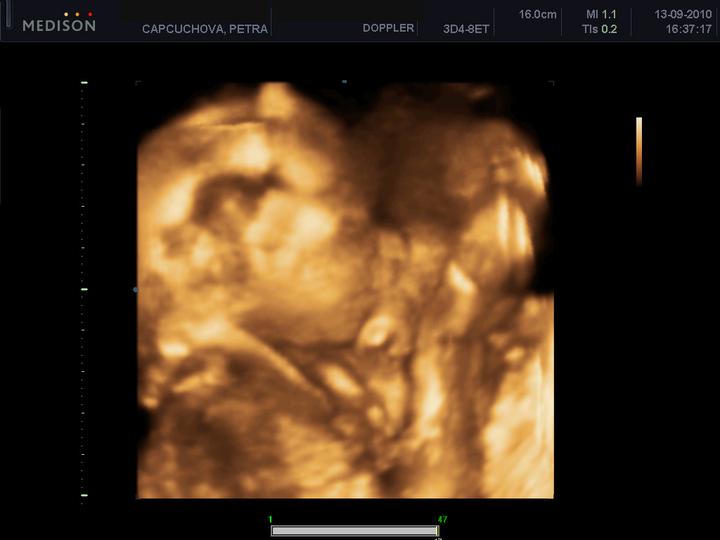

Při druhém pokusu jsme se s doktorkou dohodly, že nastoupím na dlouhý protokol, aby se mi vytvořilo víc kvalitních vajíček. Začala jsem stimulovat od půlky února a koncem dubna šla na odběr folikulů. A taky že to pomohlo, vytvořilo se víc kvalitních vajíček. V Sanatoriu jsem řekla embryologovi, jaký jsem měla posledně problém, a sama mi nabídla, že teda necháme PK na 5 dnů, aby viděli, jak se vyvýjejí a jak to zvládají. 1.5.2010 jsme si jeli do Prahy pro naše embroušky, dokonce vydrželi ještě další dva, které mi dali zamrazit do zálohy.

13.5. jsem byla na odběrech hcg, jehož hodnota byla 994, hodnota byla dost vysoka na 13. den.